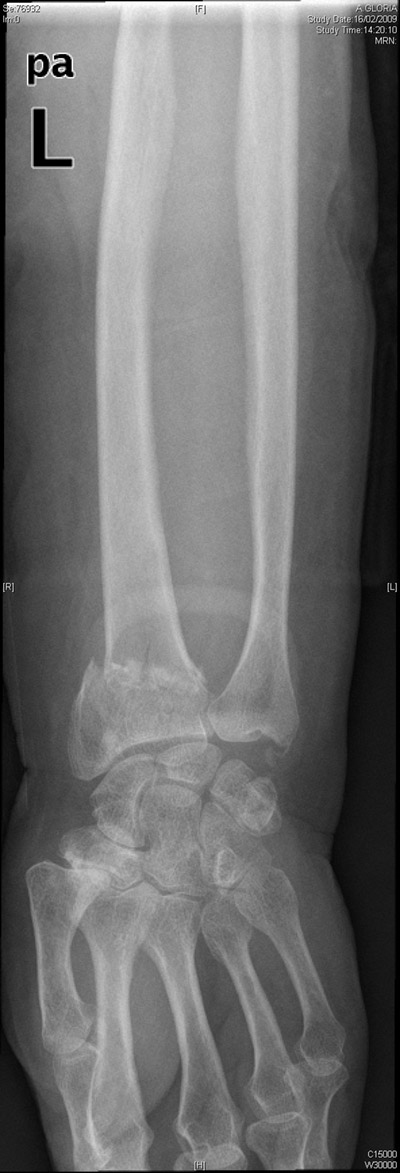

Carpo normal

ACT Alteraciones degenerativas en muñeca.